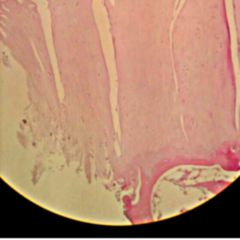

Bei der klassischen Arthrotomie müssen oft relativ umfangreich gelenknahe Weichteilstrukturen durchtrennt werden. Daher gestaltet sich der postoperative Heilungsverlauf langsamer und zum Teil auch weniger vollständig als bei der minimalinvasiven Arthrotomie. Wegen des besseren Heilungsverlaufes verdrängt die Arthroskopie die klassische Arthrotomie zunehmend. Wesentlichen Anteil daran haben entsprechende medizintechnische Verbesserungen.

In Deutschland wurde die klassische Arthrotomie bis in die 1990er Jahre bei Standardeingriffen, die heutzutage arthroskopisch durchgeführt werden (Ersatz des vorderen Kreuzbandes, Meniskusoperation etc.), eingesetzt. Heute findet die klassische Arthrotomie routinemäßig noch bei endoprothetischen Ersatzplastiken, in der Tumorchirurgie oder als Ultima Ratio bei Gelenkinfektionen statt. Auch zur Wiederherstellung der Beweglichkeit (Arthrolyse), zur Gelenkversteifung (Arthrodese) oder zu Teilsperrung eines Gelenks (Arthrorise) kann eine Arthrotomie angezeigt sein.